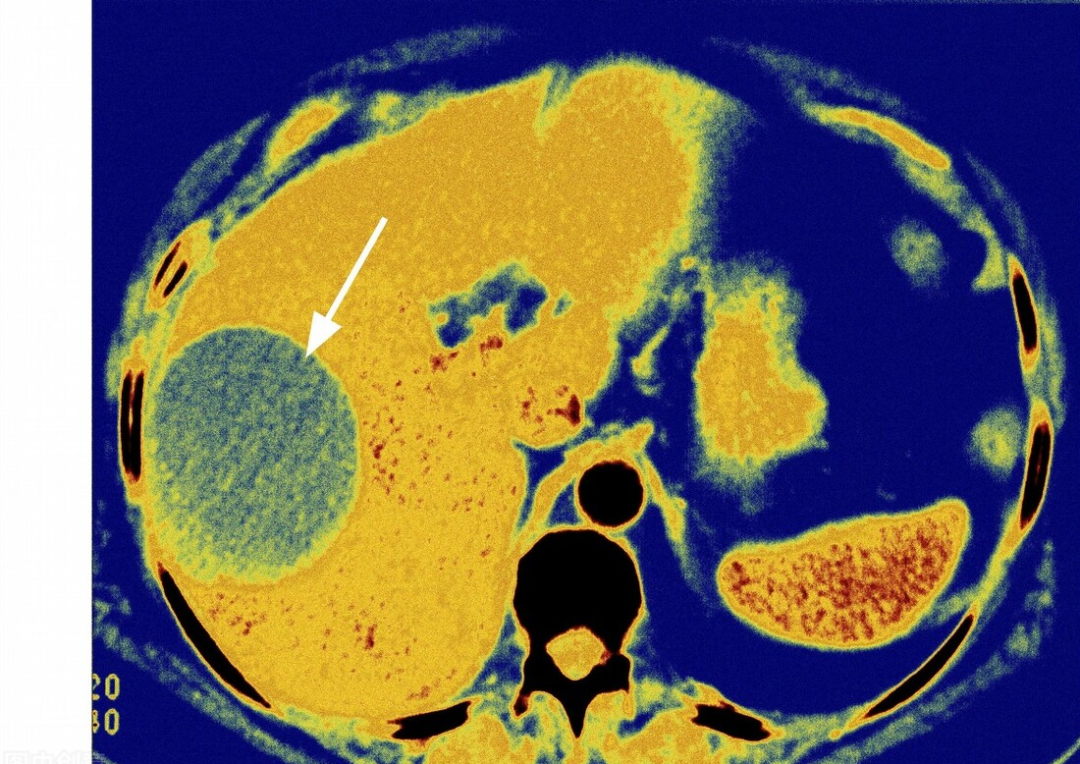

CT提示张女士的肝脏有个较大的肿块,大概有拳头这么大,可能是恶性肿瘤(肝癌),也可能是肝脓肿或者肝囊肿,不好鉴别,得进一步做增强CT,现在看起来像肝癌的可能性更大。

(此图肝脓肿并非张女士的,仅为学习使用)